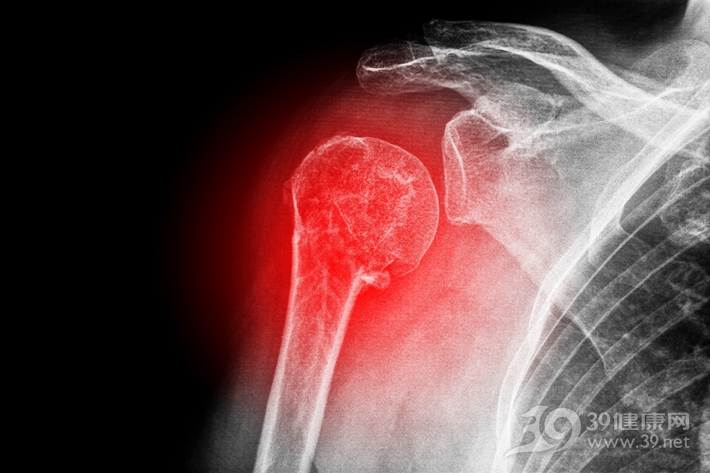

说其为天灾,也就是先天解剖因素,主要是因为肩关节是人体很特殊的一个关节,狭义的肩关节由肱骨头与肩胛盂组成。由于肱骨头直径远大于肩胛盂,且肩胛盂窝非常浅,盂肱关节就像海豹用鼻子顶着的球一样,鼻子小(肩胛盂面积小),球却很大(肱骨头很大)这样的关节结构使得肩关节处于非常不稳定的状态,当周围结构松弛或发生外伤时肩关节容易发生脱位。

此外,肩关节脱位还有以下几类情况。肩关节脱位按照脱位后肱骨头的位置,可以分为前脱位以及后脱位。其中前脱位临床最为常见,我们上述的习惯性肩关节脱位指的就是前脱位。其中前脱位又可以分为喙突下脱位、盂下脱位、锁骨下脱位以及胸腔内脱位。